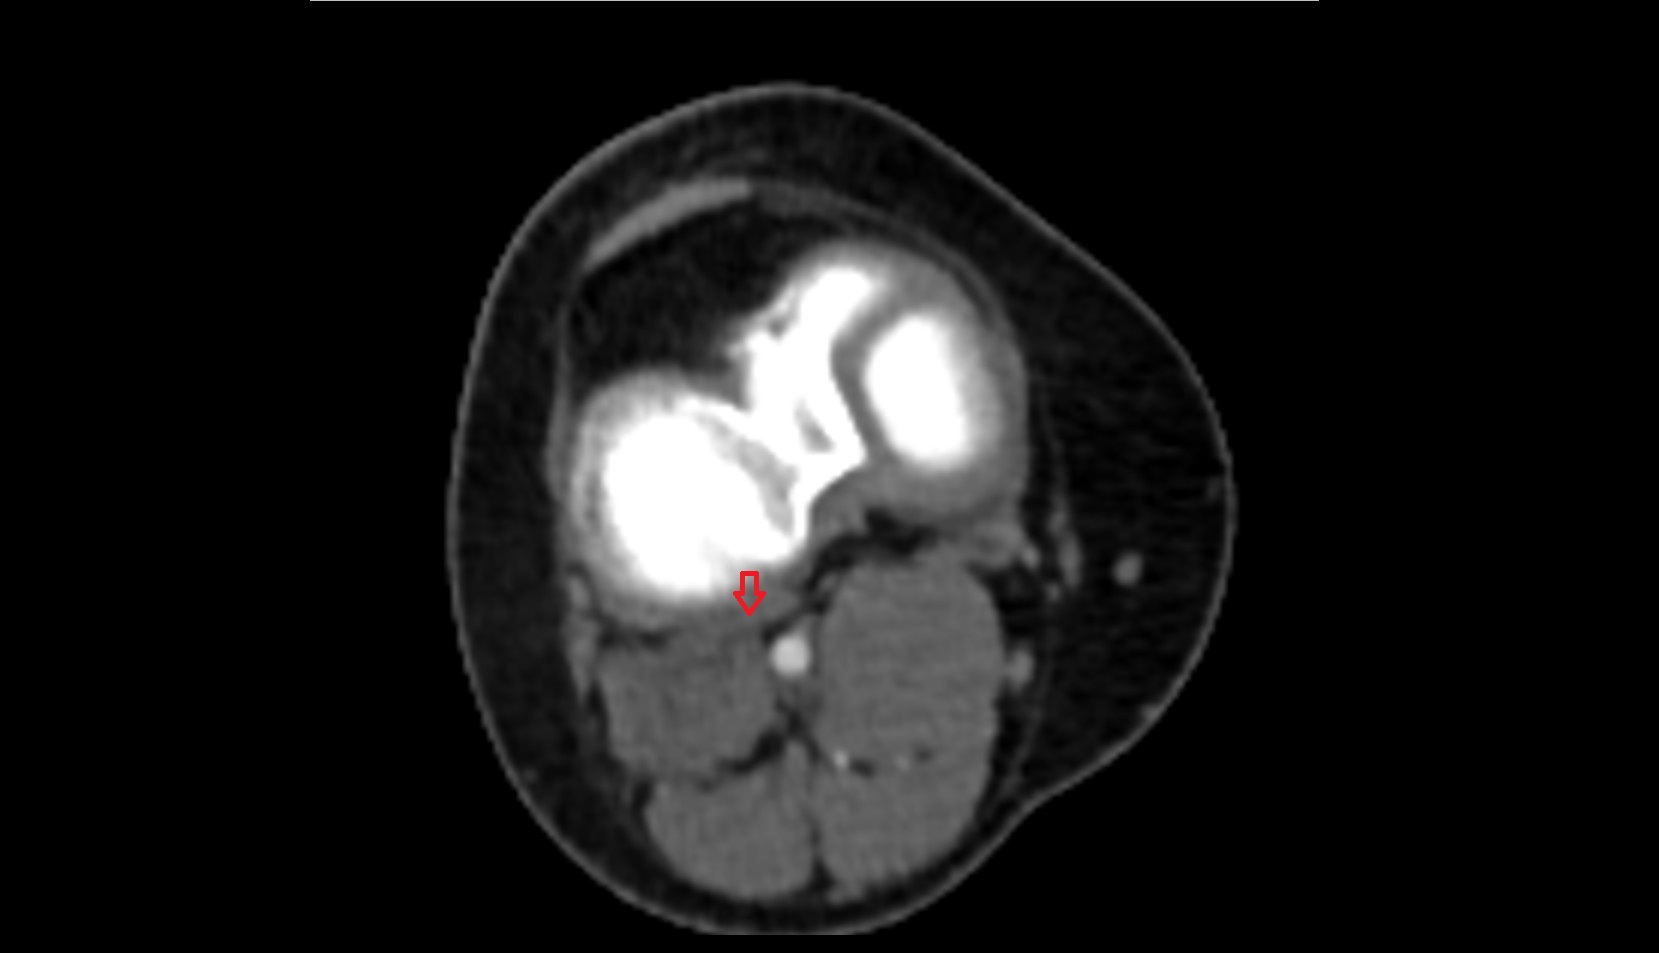

- Knee Joint

- Femoral condyle articular cartilage

- Tibial condyle articular cartilage

- Patella

- Patellar articular cartilage